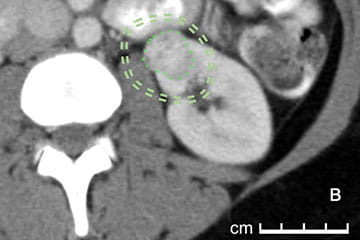

Single Slice Equation

Urology researchers created the single slice equation as a way to predict how much damage might be done to a kidney when treating kidney cancer in patients.